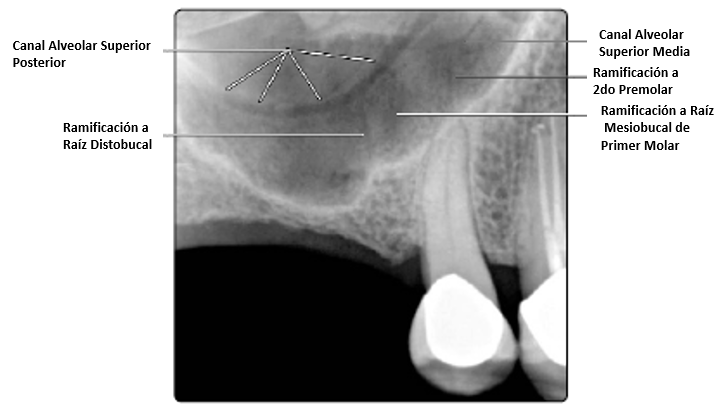

El canal alveolar posterior puede muchas veces ser visible como una línea curva que parece estar dentro del seno en radiografías periapicales del maxilar posterior. Este canal usualmente está localizado a lo largo de la pared del seno maxilar.